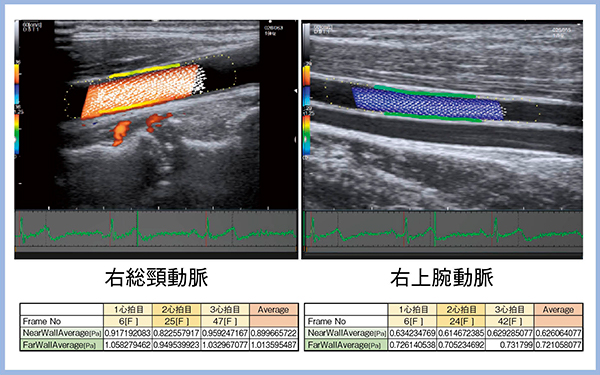

5.5th stage:血管内皮機能の観察(VFM Vascular)

LISENDO 880に新たに搭載された“VFM(Vector Flow Mapping)Vascular”では,壁面剪断応力(wall shear stress:WSS)の観察が可能である。WSSの観察により血管内皮機能を予測できる可能性や,血管内皮機能と心不全とのかかわりなどが注目されており,VFM Vascularへの期待も大きい。VFM Vascularでは,3心拍のWSSを測定し,その平均値を算出する(図2)。今後の可能性については後述する。

図2 VFM VascularによるWSSの観察